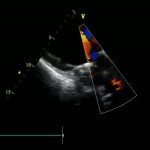

Дуплексное сканирование сосудов – современный метод диагностики заболеваний сосудов с использованием УЗИ, совмещенного с допплерографией.

Дуплексное сканирование сосудов позволяет оценить состояние стенок сосудов, просвета сосудов, обнаружить бляшки, стенозы (сужения), деформации хода и врожденные аномалии развития сосудов (гипоплазии, аневризмы). Данный способ диагностики позволяет также измерить скорость кровотока в любой точке сосудистого русла.

Дуплексное сканирование используется для определения нарушений кровотока в аорте, сосудах внутренних органов, головного мозга, шеи, глаз, верхних и нижних конечностей и т.д.

Дуплексное сканирование сосудов позволяет диагностировать сердечно-сосудистые и неврологические заболевания даже на ранних стадиях. Также в медицинском центре широко практикуется такой современный метод диагностических исследований, как денситометрия.

УЗДГ БЦА (шея) 1750р

УЗДГ транскраниальных сосудов (голова)1500р

УЗДГ БЦА и транскраниальных сосудов (шея и голова) 2600р

УЗДГ артерий верхних конечностей 1400р

УЗДГ вен верхних конечностей 1450р

УЗДГ артерий и вен верхних конечностей 2100р

УЗДГ артерий нижних конечностей 1700р

УЗДГ вен нижних конечностей 1700р

УЗДГ артерий и вен нижних конечностей 2700р